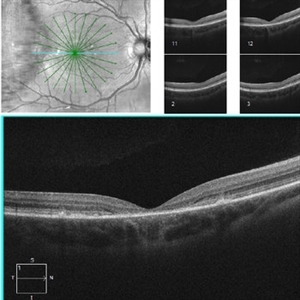

Stargardt's Disease

Stargardt's Disease

Jun 11 2016 by John S. King, MD

Outer atrophy centrally with extrafoveal hyper-reflective protrusions into the outer retina.

Condition/keywords: bull's eye maculopathy, fleck dystrophy, Stargardt disease